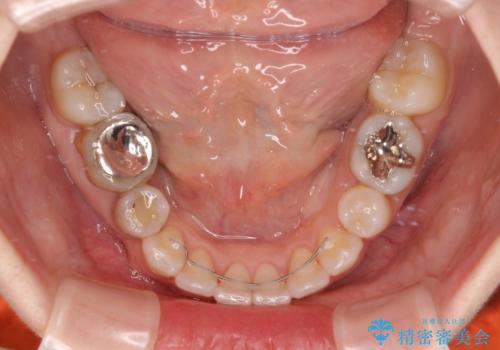

奥歯の咬み合わせ改善には1年ほどの期間と処置中の噛みにくさを強いることとなりましたが、抜歯後はスムーズに治療を完了させることができました。

歯ぎしりの際に奥歯が干渉していた咬み合わせも理想的な状態に改善できました。